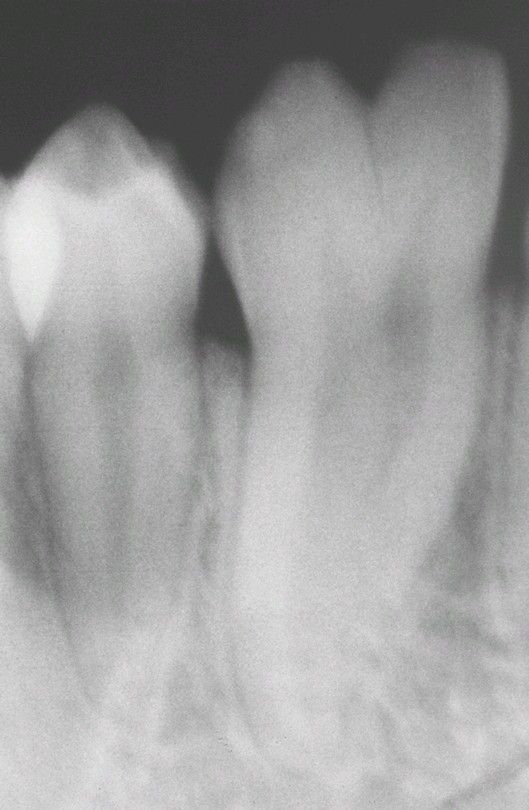

Fusion

Radiograph of the same patient depicted. Note the bifid crown overlying the single root canal; the contralateral radiograph revealed a similar pattern.